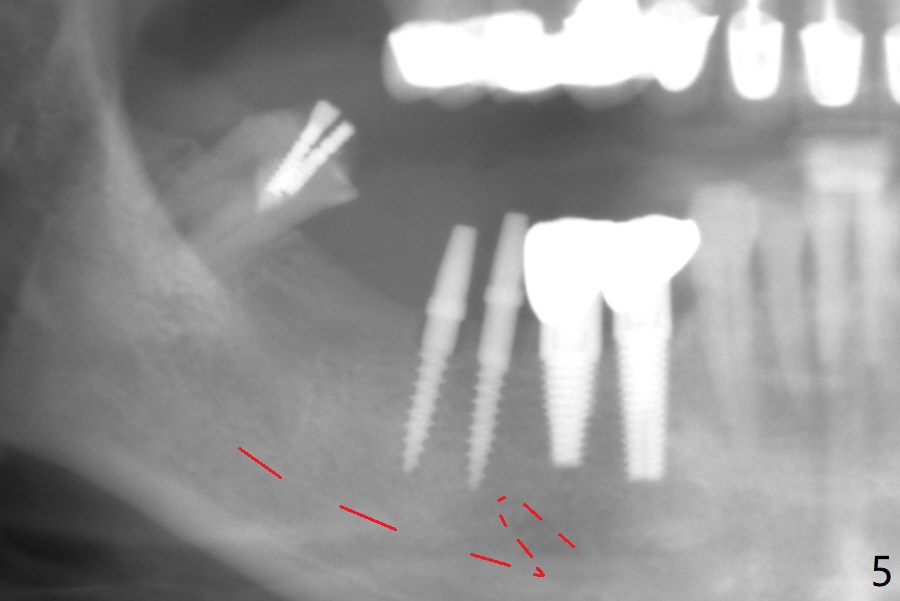

The edentulous ridge at #30 is narrow (Fig.1). After ridge reduction, osteotomy is initiated with 1.2 mm drill for 10 mm; the mesial osteotomy is to be changed (Fig.2 red line). Using a 1.2 mm drill placed in the distal osteotomy (Fig.3 D), the mesial osteotomy changes in trajectory with subsequent placement of a 2.5x10(4) mm 1-piece implant. Since the mesial implant is high in occlusion, the cuff of the distal implant is changed to be 2 mm (Fig.4 (shorter black line)). Panoramic X-ray is taken to show no violation of the Inferior Alveolar Canal (Fig.5 red dashed line). These two 1-piece implants are slightly lingually placed (Fig.6). The crestal bone around the implants resorbs without thread exposure 5 months postop (Fig.7). Impression is taken for a splinted crown (Fig.8-12). There is no metal show around the 2.5 mm 1-piece implants 6 months postop (advantage) vs. that at #28 and 29 (Fig.13). Bitewing is taken post cementation to determine whether residual cement is present (Fig.14). There is periodic swelling and pain in the lower right quadrant 2 years post cementation (Fig.15). In fact periimplantitis appears to have developed at #28 (Fig.16) with loss of the buccal bone (Fig.17,18). The buccal bone loss is less at #29 (Fig.19) and #20 (Fig.23) and no at #30 mesial and distal implants (Fig.20,21). A much smaller implant will be placed lingually at #28 immediate (Fig.24,25).